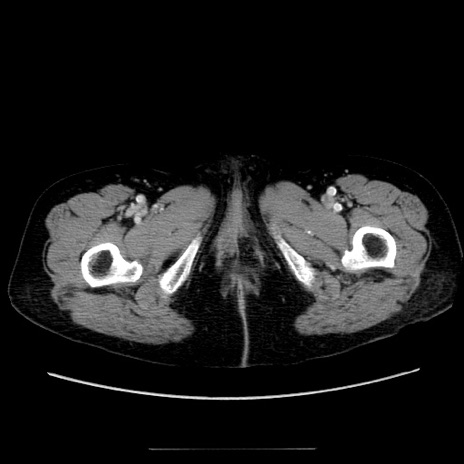

症例5(横断像)

【症例】70歳代女性

【主訴】お腹が張る

【現病歴】1週間くらい前から腹部膨満の自覚あり。昨日夜から増悪したため、本日救急外来受診。

【身体所見】意識清明、BT 36.5℃、BP 165/106mmHg、HR 80bpm、SpO2 98%、腹部:膨満、軟、自発痛・圧痛なし、触診にて不快感あり、腸蠕動音:減弱

【データ】WBC 12600、CRP 1.04